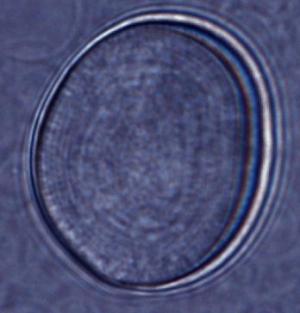

Kohane a avut ideea să izoleze anestezicul în lipozomi. Lipozomii sunt sfere cu diametrul de 20-30 de nanometri formate dintr-un strat dublu de fosfolipide, membrana lipozomală fiind asemănătoare cu cea a celulei. Ei au proprietatea interesantă că izolează un mediu apos într-o membrană hidrofobă (ce conţine substanţe care nu formează legături chimice cu apa). Datorită acestor proprietăţi, lipozomii sunt deja folosiţi pentru a transporta medicamente în corp, printre care şi tratamente anticancer.

Un lipozom în care s-a injectat saxitoxin, un anestezic puternic: administrând o astfel de combinaţie în corpul unui şoarece, se poate obţine o anestezie locală ce durează câteva zile.

Credit: Spitalul de Pediatrie din Boston